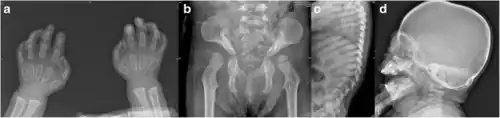

a-c)Radiographs of 21-month-old with I-cell diseae